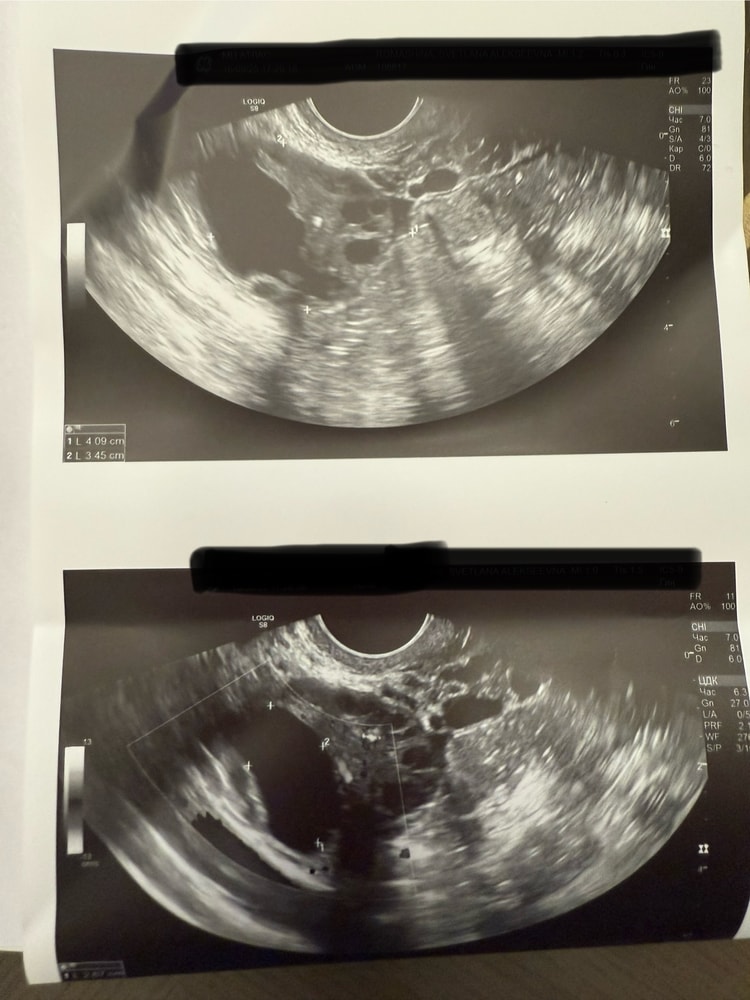

УЗИКраткая справка. У меня МФЯ. Овуляция если приходит, то это уже успех. Вот сегодня 36 дц. Примерно 2 дня назад поняла , что идет овуляция.

Сегодня решила удостовериться и сходила на УЗИ в ближайшую клинику.

Врач окончательно так и не сказала что это, ДФ или ЖТ. (Форма то странная) Хотя и сказала , что кровоток есть, но слабый и по краям.

Что скажете?